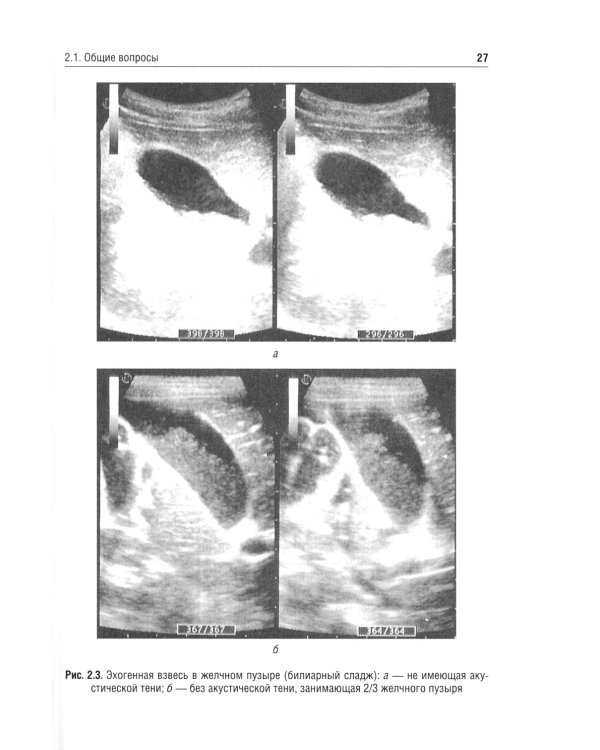

В учебном пособии рассмотрены отдельные морфофункциональные особенности билиарного тракта, вопросы физиологии желчеобразования и желчеотделения, а также представлены материалы, касающиеся диагностики и лечебной тактики дискинезий желчевыводящих путей, хронического холецистита и желчнокаменной болезни. Приведены анамнестические, клинические и дополнительные критерии диагностики, позволяющие оптимизировать диагностическую тактику, а также программы назначения лечебно-коррекционных мероприятий с учетом индивидуальных и возрастных особенностей пациента. Отражены сведения, касающиеся новых клинических вариантов течения билиарных дисфункций у детей, - диспластикоассоциированных дискинезий желчевыводящих путей. Пособие предназначено студентам медицинских вузов, а также врачам-педиатрам, гастроэнтерологам, терапевтам, врачам общей практики.| Издательство | ГЭОТАР-Медиа |